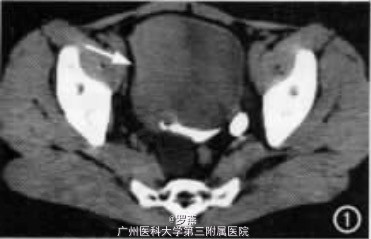

腹部平片示膀胱区可见一年轮状6. 5cm X 4. 2cm 大小密度增高影,其边缘光滑锐利。静脉肾盂造影所见:两侧肾影轮廓增大 ,左肾盂 、肾盏充盈饱满 ,左输尿管扩张,右肾无充盈。IVP 后行 CT 检查示膀 胱腔内一约9.0cm X5.0cm X5.0cm 的软组织肿块,宽基底附于膀胱右侧壁(图 1), 近膀胱颈部后侧一巨大同心圆状结石,大小约5. 8cm X 4. 4cm X 4. 0cm,与膀胱后下壁粘连、固定(图 2)。双侧输尿管扩张,右侧明显,内见一直径0. 8cm 的结石影,右肾扩大,肾盂积水,肾实质菲薄。

手术所见:膀胱内尿液约 20mI,呈血性,膀胱右侧壁一约14. 0cm X 9. 0cm X 9.0cm大小肿瘤,充满整个膀胱,近膀胱颈部有一 6. 0cmX 5. 0cm X 5. 0cm 大小结石。左输尿管直径约1. 0cm,右输尿管粗大,直径约 2. 0cm。病理标本:膀胱约12. 0cm X 10. 0cmX 10. 0cm大小,其内充填10. 0cm X 9. 0cm X 9. 0cm 大小广基底物,右输尿管开口及膀胱右侧壁均被侵及,膀胱内有一约6. 0cm X 5. 0cm X 5. 0cm 大小结石。病理诊断:膀胱蕈样移行细胞癌( 三级 ),累及膀胱壁全层 ;膀胱结石 。